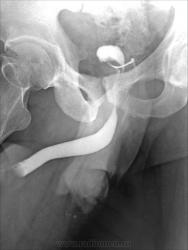

очень похоже на свищ между уретрой и венозной системой полового члена(кавернозными телами) - на последнем снимке есть верху вены.

А, если предположить, что "это" грыжа7

Случай, хоть и довольно "старый", как и сам пациент преклонного возраста, но довольно интересный. Это наблюдение одного из наших коллег, работающего в качестве преподавателя одной из медицинских Академий. Случай имеет название - "Пузырно - мошоночная грыжа".